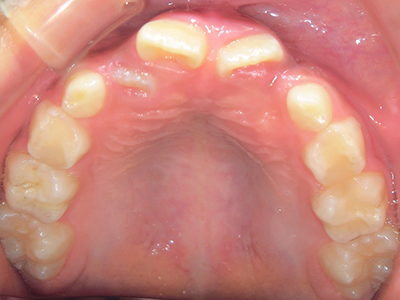

小児矯正について

歯並びの相談に来られるお子様は、口呼吸をしているケースが多く、これが歯並びに大きな影響を与えています。

ないき歯科クリニックでは、上あごの成長不足を補い、鼻呼吸を獲得しつつ歯列を整え、将来のお口をより健康な状態にすることをゴールに定める矯正治療をおこなっています。